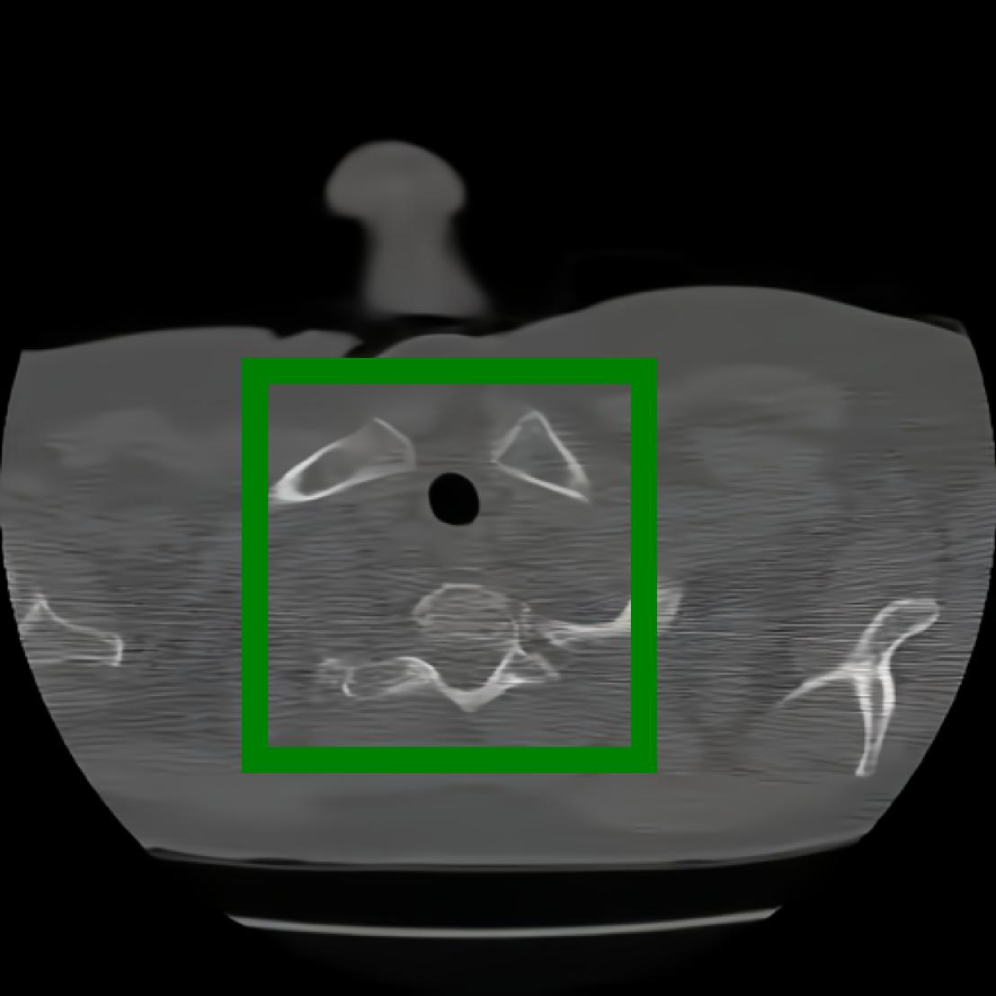

In addition, we use the CT Heart Segmentation dataset [NikhilTomar], which contains a series of 2D computed tomography (CT) heart scans with the resolution of 512 ×\times 512. This dataset provides clear anatomical structures of the human heart, and is widely used in medical image segmentation and compression tasks. Its inherent slice-based nature naturally aligns with our patch-based INR compression strategy, allowing us to further evaluate the effectiveness of COLI for medical images with rich structural information.

Figure 12: The visual comparison of different compression methods on another CT Heart Segmentation image.

Figure 13: Zoomed-in view of the highlighted region in Figure 12.

IV-B3 Visual Comparison

Figures 7 and 8 present representative examples from the CIL dataset and their zoomed-in regions, respectively. For the CT Heart Segmentation dataset, Figures 10 and 12 illustrate typical reconstruction results, while Figures 11 and 13 further enlarge local regions to compare structural details. Across both datasets, COLI preserves fine structures and global continuity well even at relatively low bpp. Specifically, on the CIL dataset, COLI attains the lowest bitrate among INR-based methods while still maintaining clear texture details. On the CT Heart dataset, COLI also operates at a low bpp within the INR family and delivers superior visual quality with improved detail fidelity and smoother structural presentation. The zoomed-in regions show fewer blocking artifacts and smoother transitions, making COLI especially suitable for large images and medical images. These visual results validate that INR-based compression can achieve efficient storage with reliable perceptual consistency, offering practical advantages for real-world large-scale image processing.